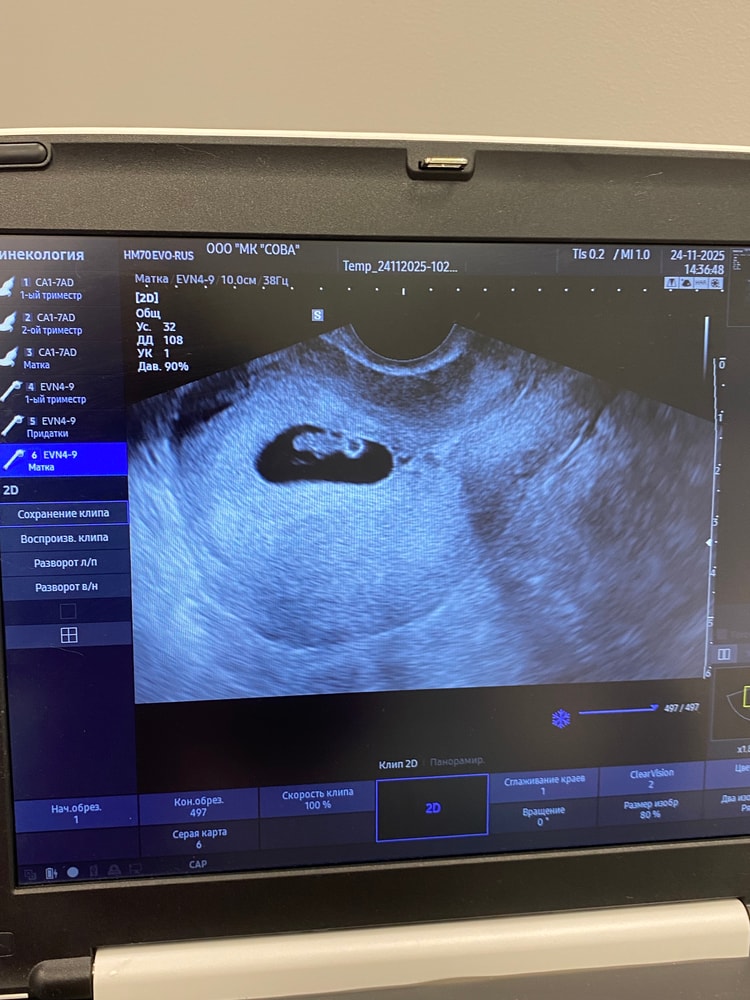

31 дпп УЗИ мой маленький так подрос за 10 дней

Результаты УЗИКак же мы счастливы, сердечно хорошо бъётся🥹 наш малыш так вырос за 10 дней я даже не ожидала🫶! Подарили нам носочки в клинике, так приятно💕💕💕 через недельку на учет пойду вставать🤰Забыла написать из поддержки оставили утрожестан 400Х2 до 12 недель, и масляный прогестерон через день теперь колоть неделю, потом через два дня!